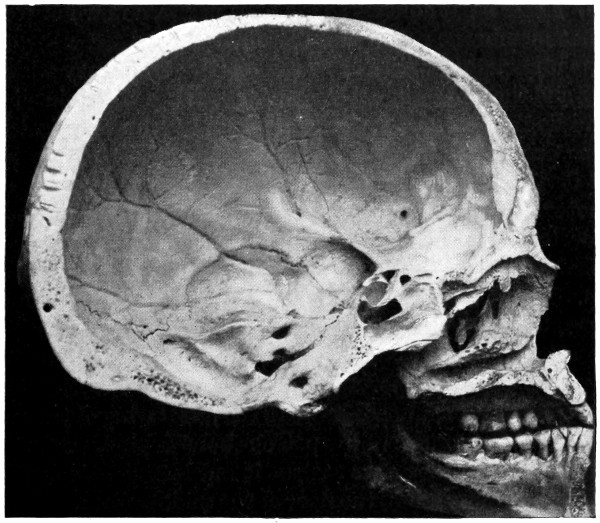

| 29 A and B. The base of the skull and the base as seen on transillumination | 70, 71 |

| 50 A and B. The inner aspect of the skull and the same seen on transillumination | 137 |